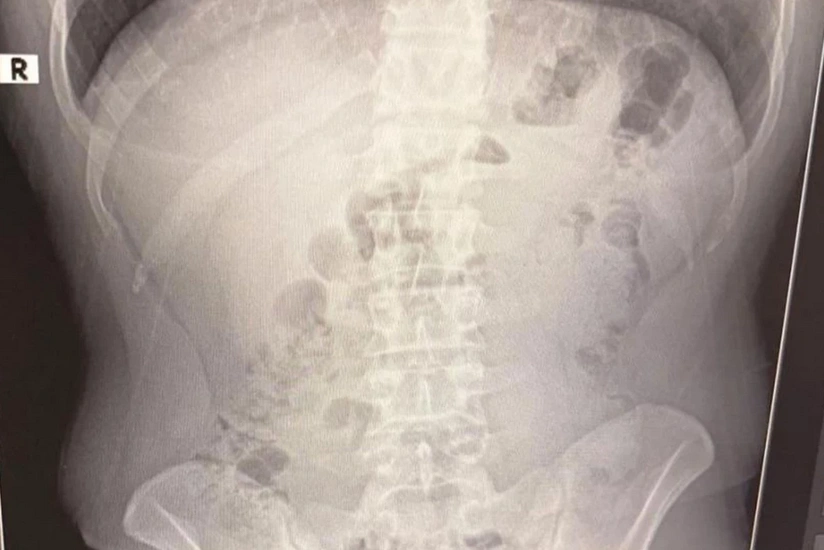

Şübhəlilər xəstəxanaya aparılıb. Rentgen müayinələrində onların mədəsində kapsul içində gizlədilmiş metamfetamin aşkar edilib. İran vətəndaşları barəsində məhkəmə həbs qətimkan tədbiri seçib.